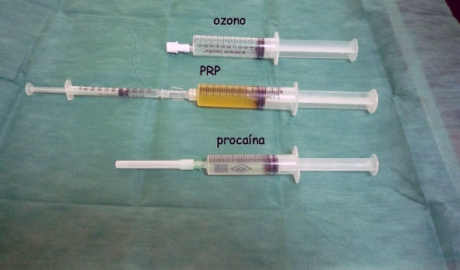

- 2007: Comenzamos a aplicarlo combinado con el ozono para potenciar sus efectos y mejorar su protección antimicrobiana (J.Cabot).

- Cabot J et al. Tecnica conbinada de factores de crecimiento y ozonoterapia en la artrosis de rodilla. Primer congreso de AEPROMO. Nuevos horizontes en ozonoterapia, Pontevedra, 5 de Junio, 2009